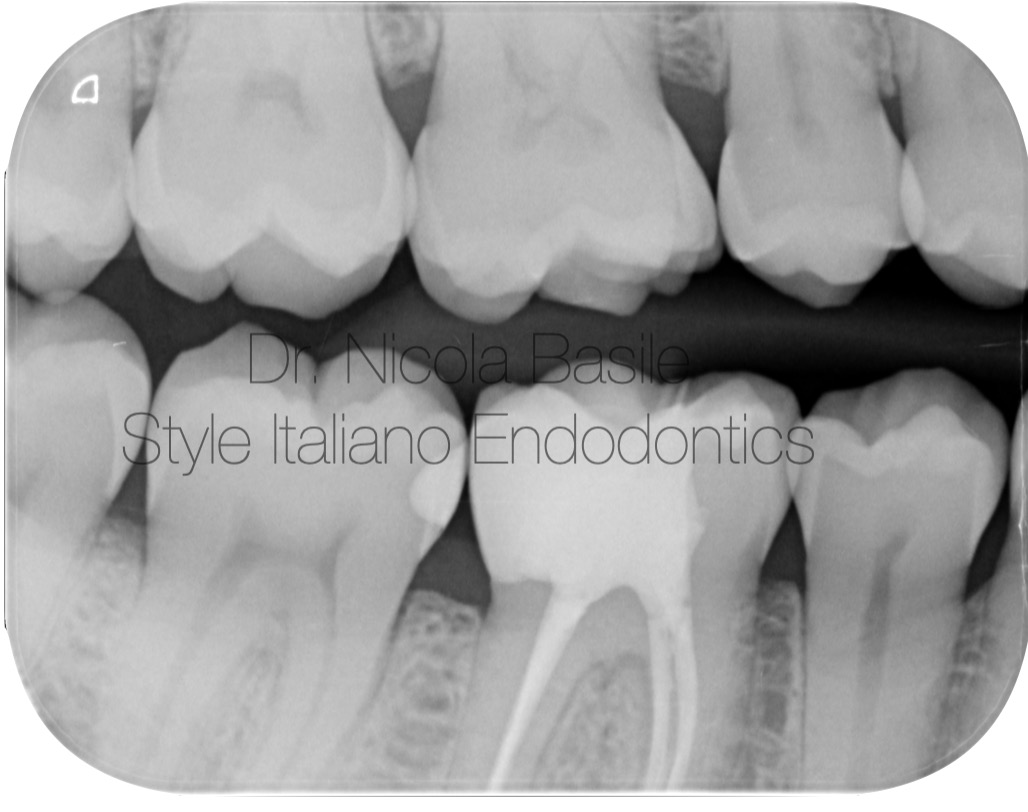

At the following appointment, two days later, after complete removal of the glass ionomer cement and any remaining carious tissue, crown lengthening was performed.

This procedure, performed in a patient without periodontal disease despite suboptimal oral hygiene, involved minimal removal of periodontal tissues and the underlying bone solely at the interproximal bone peak adjacent to the carious lesion. The aim was to expose more of the tooth structure to facilitate subsequent restorative procedures.

Thanks to the provisional restoration performed with glass ionomer cement, the gingival tissues appeared less inflamed compared to the initial appointment. As demonstrated in the videos, this conferred a significant advantage during the surgical procedure by substantially reducing bleeding throughout the surgical maneuvers.

In the video, following flap elevation, the residual height of healthy tooth structure, subsequent to carious lesion removal, is assessed in relation to the surrounding bone tissue. This height is deemed insufficient to support an adequate reconstruction of the supracrestal attachment apparatus.

In this video video, following the completion of osteotomy and osteoplasty, an increased height of tooth structure is observed, which will facilitate the appropriate reconstruction of the supracrestal attachment apparatus of the supporting tissues.

Fig. 4

During the same appointment, following isolation with a rubber dam, the distal canal was obturated using a single cone and bioceramic cement.

After obturating the distal canal, the chamber was cleaned using burs and rinsed with glycine powder. This is the appearance prior to the application of adhesive techniques and the composite build-up.